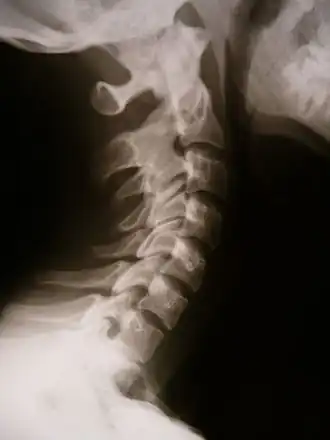

![]() X-ray showing synostosis in the cervical spine | |

Synostosis (from Ancient Greek συν- (syn-) 'together' and ὀστέον (ostéon) 'bone'; plural: synostoses) is fusion of two or more bones. It can be normal in puberty (e.g. fusion of the epiphyseal plate to become the epiphyseal line), or abnormal. When synostosis is abnormal it is a type of dysostosis. Examples of synostoses include: